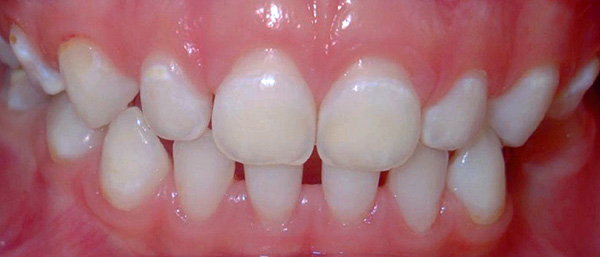

A foto mostra um exemplo de cárie no estágio de uma mancha branca nos dentes da frente de uma criança:

É essa etapa do processo carioso que pode ser revertida com um conjunto oportuno de procedimentos de recuperação - remineralização e fluorinação. Com o amolecimento adicional do esmalte, sua estrutura é destruída irreversivelmente, a cárie superficial é formada e, com o tempo, as bactérias começam a destruir a dentina.